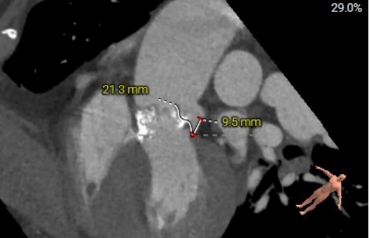

左冠高度:9.6mm

左冠瓣叶长度:21.3mm

患者为老年男性,合并慢性阻塞性肺疾病、胸腔积液及陈旧性脑梗,外科手术风险高。主动脉瓣重度狭窄及合并反流,瓣口面积小,术中跨瓣有一定难度。术中采用局麻方式,降低麻醉风险,计划采用25mm球囊进行预扩张,根据预扩张情况选择25mm/28mm的杰成主动脉瓣膜,植入瓣膜后根据瓣膜形态及血流动力学参数决定是否进行后扩张。患者左冠开口高度偏低,为9.6mm,杰成瓣膜总体冠脉闭塞风险较低,但术中仍需评估冠脉风险。另主动脉瓣环夹角53°,存在横位心,预估手术难度较大,术中需注意器械同轴性。